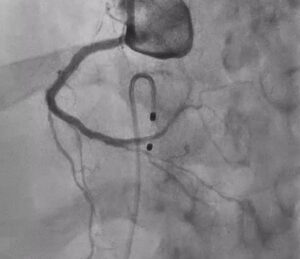

Post Rota with Calcium Fracture ☝️

After exchanging to a dedicated rota wire, the next step was rotational atherectomy, performed in a segmental manner from the proximal RCA up to the crux.

This was the key turning point in the case.

In diffuse calcified disease, especially in CTO segments, adequate lesion preparation is what determines whether the rest of the PCI will be smooth or compromised. Without sufficient calcium modification, balloon expansion remains poor, device delivery is difficult, and final stent expansion may be suboptimal.

The aim of atherectomy here was not simply to “debulk,” but to create a more modifiable pathway through a long, resistant, heavily calcified vessel. In lesions like this, atherectomy plays a crucial role in transforming an undilatable artery into one that can be prepared properly for definitive PCI.